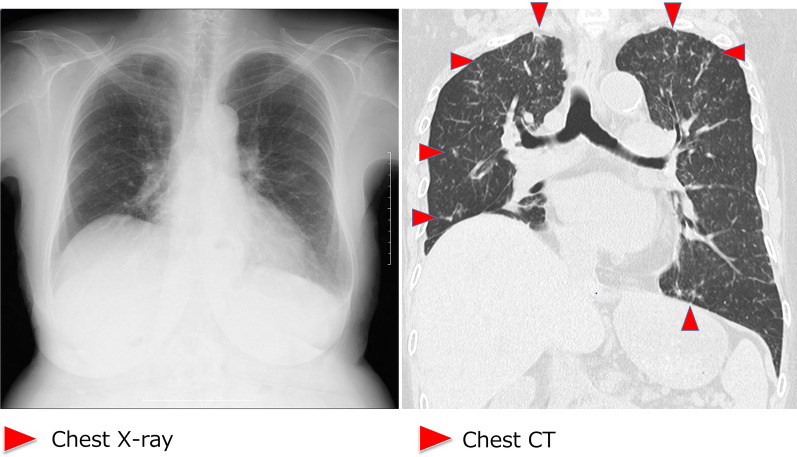

During supportive blood transfusion therapy, her condition was complicated by the following three infectious diseases: nontuberculous Mycobacterium (NTM) infection, pulmonary aspergillosis, and Escherichia coli bacteremia. The course of each of these diseases is summarized as follows. (1) NTM: In August 2020, she complained of hypoxemia (SpO2 level, 91%) and fever (37.5–37.9 °C). She visited the outpatient clinic at our hospital, and initial chest X-ray revealed multiple small granular shadows in both lungs (Fig. 2). She was positive for anti-MAC antibodies, and PCR was positive for Mycobacterium avium in the sputum. We thus diagnosed her with NTM infection. She received triple anti-Mycobacterium (azithromycin, rifampin, and ethambutol) treatment for 2 weeks. Consequently, the pulmonary granular shadows reduced, hematopoiesis recovered (with normalized platelet and erythrocyte counts), and precursor cell count in the peripheral blood decreased. This spontaneous remission status persisted for 3 months. Bone marrow examination was performed during the first spontaneous remission. Blast count was 4.6%, and chromosomal abnormality with del(5q) were detected in 2 of 20 analyzed cells (10%). Background myelodysplasia persisted, with hypogranular neutrophils, pseudo Pelger–Huet anomaly, megaloblastoid changes, ringed sideroblasts, and micromegakaryocytes. Flowcytometry detected a scanty of stem cell clones (1.8%) expressing abnormal phenotypes; HLA-DR+, CD13+, CD34+, CD117+, all of these are originally expressed aberrant phenotype. This result indicated that she achieved hematological remission with cytogenetically minor residual disease. (2) Pulmonary aspergillosis: In March 2021, she presented with fever (38.4 °C) and hypoxemia (SpO2 level, 93%) again. She was treated with levofloxacin for a few weeks, but it did not relieve her fever. In April 2021, chest X-ray revealed pneumonia, with a 43 mm-diameter nodule in her left upper lobe (Fig. 3). She showed elevated levels of β-d-glucan and Aspergillus antigen, suggesting pulmonary aspergillosis. She was treated with itraconazole followed by voriconazole for 20 days, after which inflammation and the lung nodule diminished. Following treatment, hematopoiesis recovered and blasts disappeared from the peripheral blood. The del(5q) clones in the bone marrow were detected in 2 of the 20 analyzed cells. She remained in the state of spontaneous remission for 5 months. (3) E. coli bacteremia: In December 2021, she presented to the outpatient clinic with a fever of 38.4 °C; she was positive for blood procalcitonin (1.55 ng/mL). We assumed that she had sepsis and thus hospitalized her on the same day. Upon hospitalization, ESBL-positive E. coli was detected in two sets of blood cultures, and meropenem treatment was provided. On day 10 of hospitalization, cellulitis of the right lower extremity developed with neutrophil recovery, and ESBL-positive E. coli was detected in the subcutaneous abscess at the same site (Fig. 4). The antimicrobial susceptibility to the isolated E. coli is shown in Fig. 4.

Fig. 2.

Chest X-ray and chest CT imaging of the non-tuberculous Mycobacterium-infected lungs. Images show multiple granular infiltration in the pleural side of all lung fields. Red arrow-heads indicate infiltration